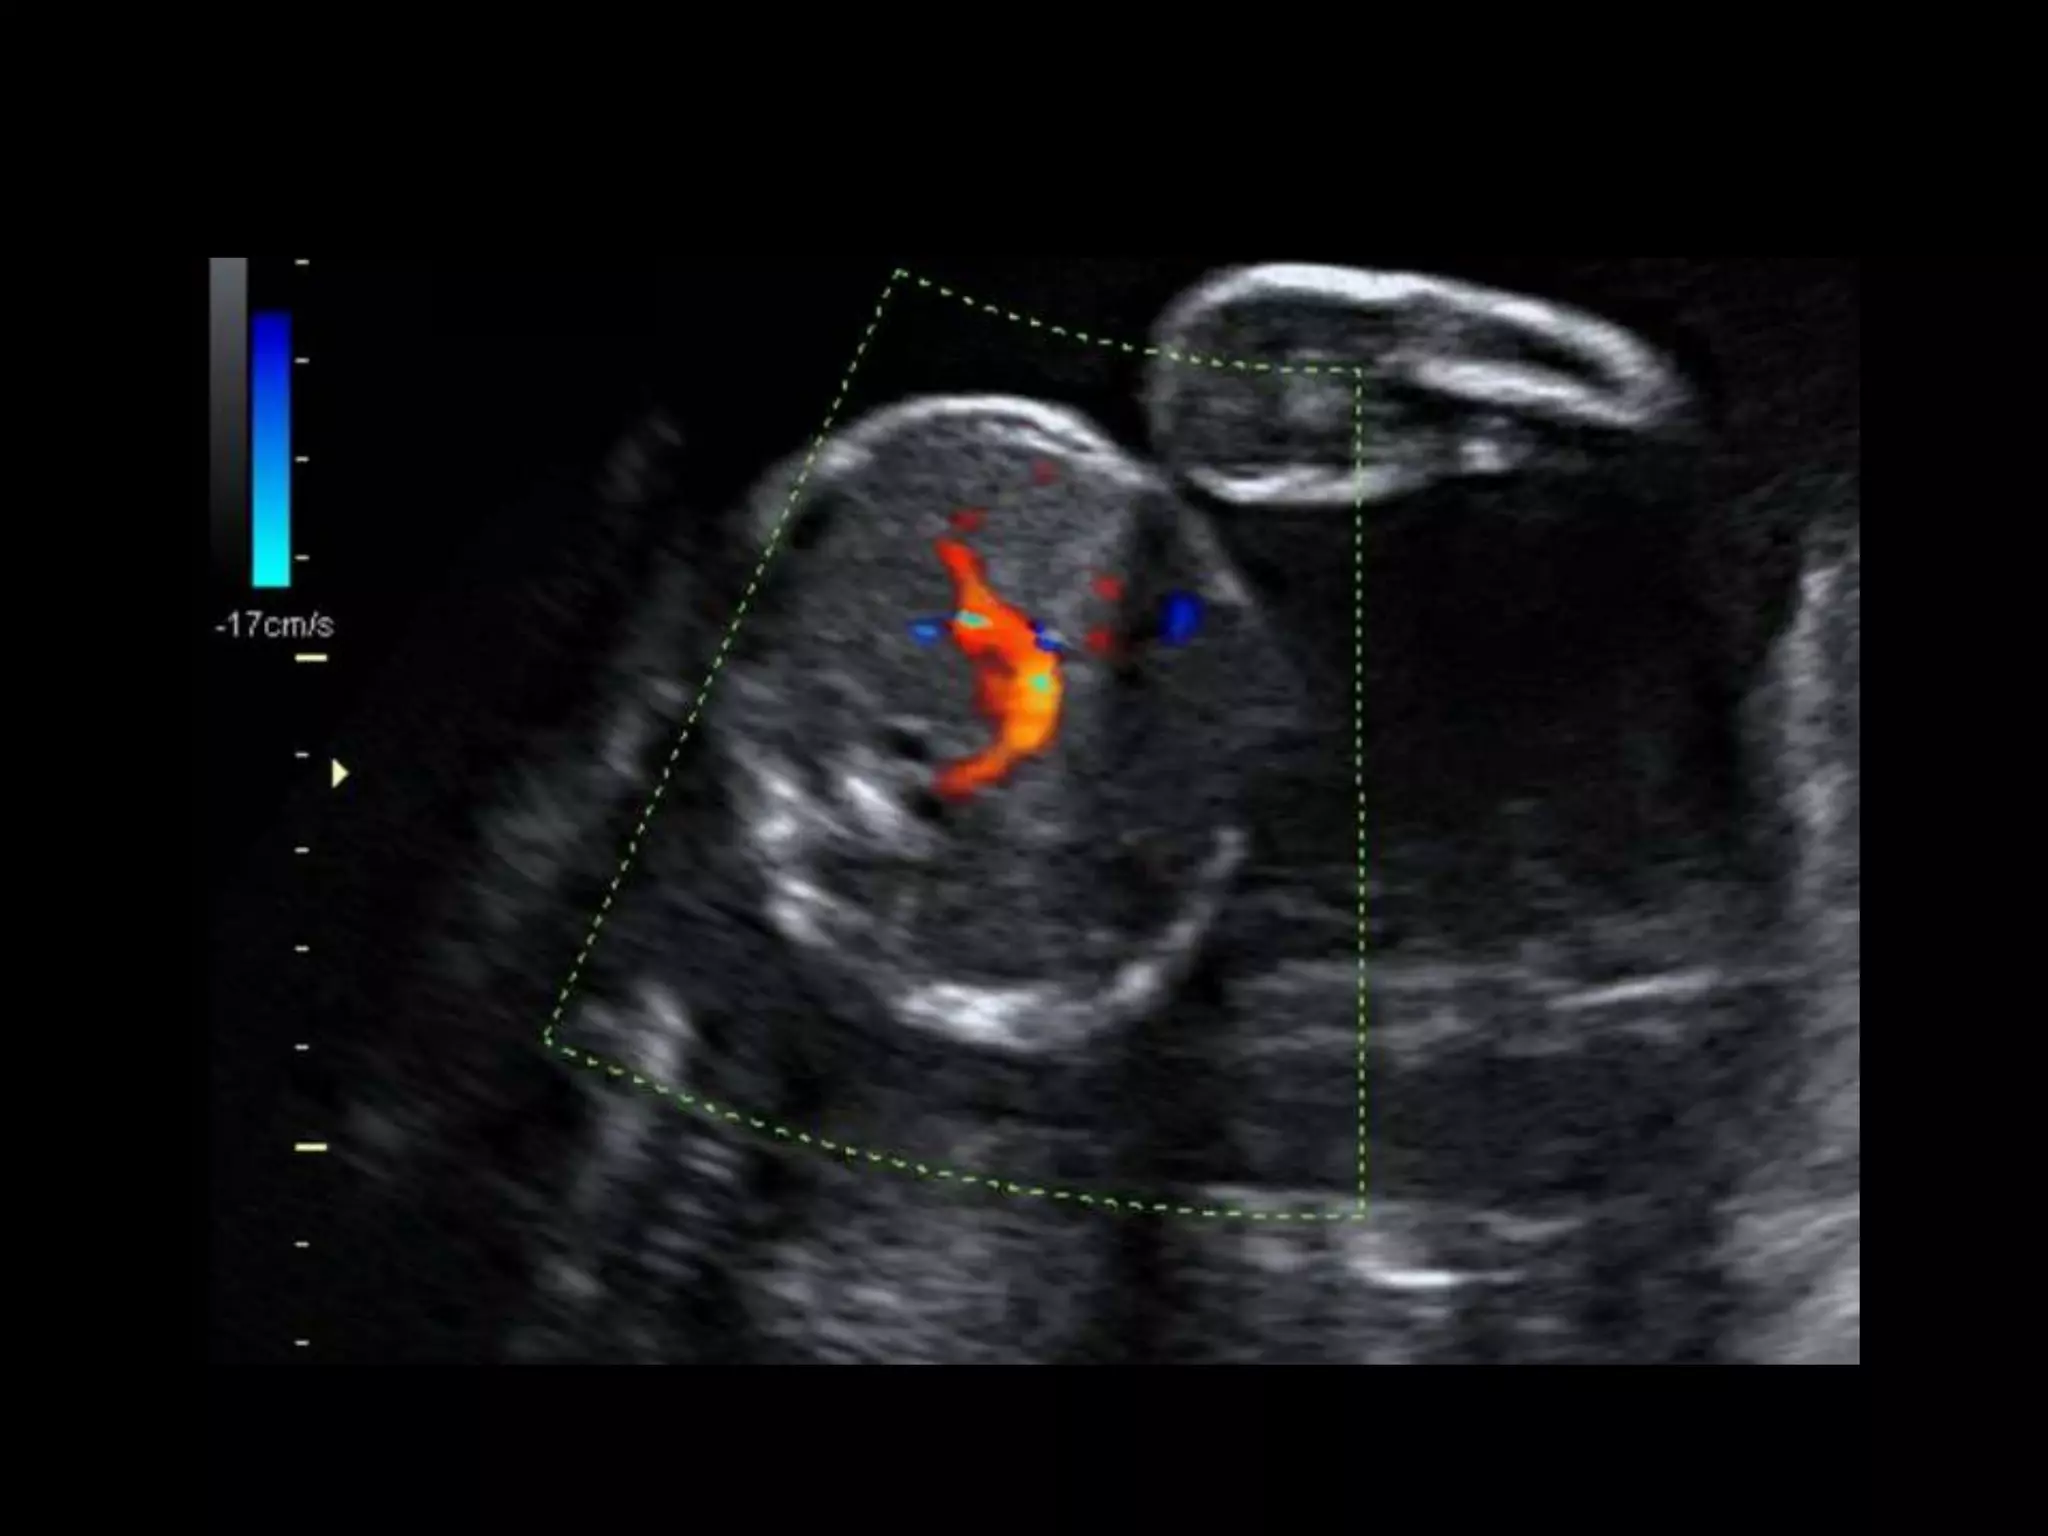

HISTORY

โ€ข 40 yo female 8.5 weeks pregant

โ€ข S/P D&C for pregnancy implanted at site of

c-section scar

โ€ข 6 weeks post D&C patient presents with

heavy persistent bleeding

โ€ข For Pelvic US

โ€ข HCG = 451 mIU/mL

D&C complicated by Perforation,

AVM w RPOC at Site of Perforation

โ€ข AVM โ€“ Acquired or Congenital

โ€ข Acquired

โ€“ Traumatic โ€“ D&C, TAB, uterine surgery

โ€“ Less common: Endometrial / Cervical CA, GTD

โ€“ Clue on US: numerous tortuous vessels, high velocities

โ€ข Tx:

โ€“ transcatheter arterial embolization

โ€ข Potential to preserve fertility

โ€“ UA ligation, hysterectomy

HISTORY โ€ข 40 yofemale 8.5 weeks pregant โ€ข S/P D&C for pregnancy implanted at site of c-section scar

• 42.

โ€ข 6 weekspost D&C patient presents with heavy persistent bleeding โ€ข For Pelvic US โ€ข HCG = 451 mIU/mL

• 50.

D&C complicated byPerforation, AVM w RPOC at Site of Perforation โ€ข AVM โ€“ Acquired or Congenital โ€ข Acquired โ€“ Traumatic โ€“ D&C, TAB, uterine surgery โ€“ Less common: Endometrial / Cervical CA, GTD โ€“ Clue on US: numerous tortuous vessels, high velocities โ€ข Tx: โ€“ transcatheter arterial embolization โ€ข Potential to preserve fertility โ€“ UA ligation, hysterectomy

POST PROCEDURE S/P embolizationof right UA and left UA due to cross collateralization

1 month followup HCG < 5 mIU/mL No flow in area โ€“ smaller in size Felt residual hematoma Will continue US follow up